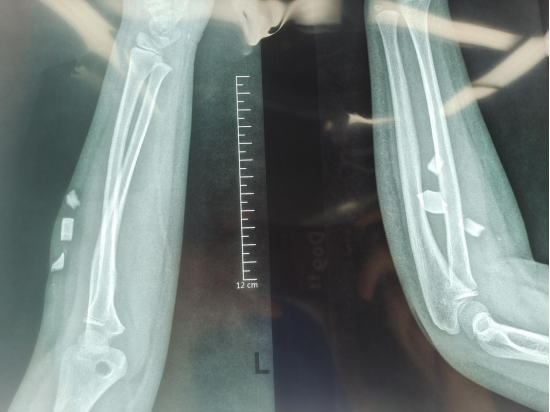

经手足外科接诊检查后,结合影像评估,确诊为"左前臂屈肌群内多发玻璃异物残留"。影像显示异物分布范围广、层次深,最大碎片达2.1cm×0.8cm。考虑到患儿年龄小、异物存留时间长、玻璃材质易碎等特点,医疗团队制定了周密手术方案。